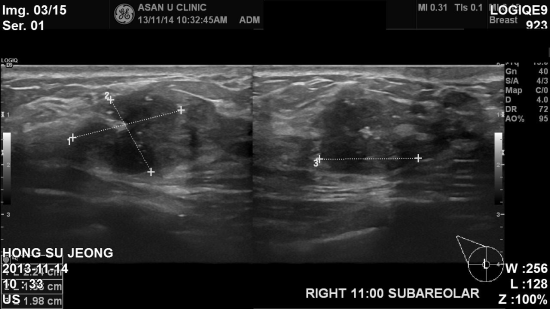

, 초음파검사상

우측유방 유두

밑 부분으로

2cm 가 넘는 혹이 발견되어

조직검사결과 침윤성유방암으로

진단되었습니다

.